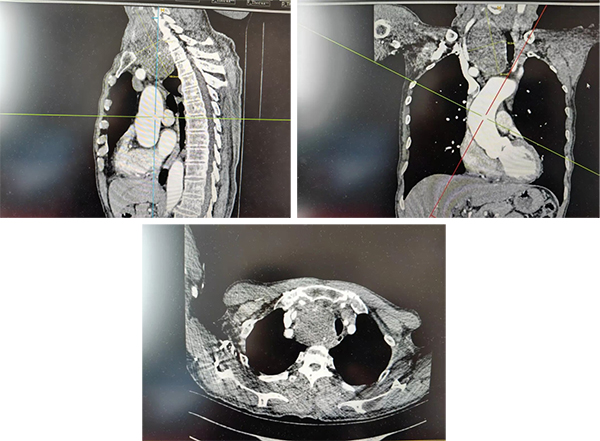

据悉,患者就诊时,甲状腺右侧叶已长出一枚巨大肿物。检查显示,该肿物最大直径约10cm,且大部分降入胸骨后,位置极深,解剖结构复杂给治疗带来极大挑战。更棘手的是,长期受巨大肿物压迫,患者气管严重左偏,呼吸功能明显受损;若不及时手术干预,肿物持续增大可能进一步压迫大血管、神经等重要组织,随时可能危及生命。然而,颈胸交接区域血管神经密集,胸膜顶结构复杂,加之肿物体积巨大、位置特殊,常规手术入路难以触及病灶,手术难度极高、风险极大,对手术团队的技术水平和协作度提出了严峻考验。